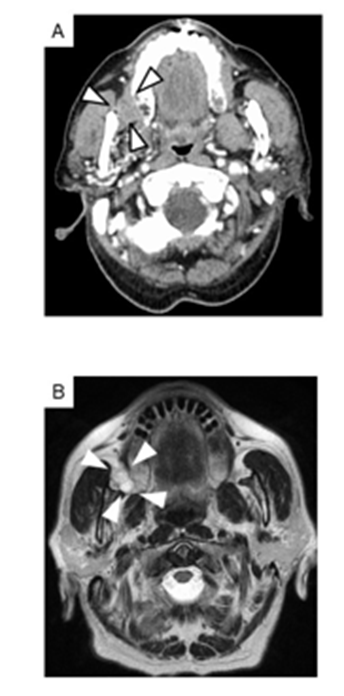

The surface mucosa was normal except for a small ulcer presumed to be the site of the previous cytology. Contrast-enhanced CT revealed a 28 × 20-mm heterogeneously enhancing mass (Figure. 2A).

Figure 2: Imaging findings.

(A) Contrast-enhanced computed tomography revealed a 28 × 20-mm mass with heterogeneous internal enhancement in the right buccal region.

(B) Contrast-enhanced magnetic resonance imaging demonstrated a well circumscribed, submucosal lobulated mass with high signal intensity on T2-weighted images. The lesion showed low cellularity, an internal reticular pattern, and marked contrast enhancement.

Magnetic resonance imaging (MRI) demonstrated a strongly enhancing, well defined, lobulated T2-hyperintense lesion with an internal reticular pattern (Figure. 2B). 18FDG-PET /CT showed focal uptake in the buccal lesion only (Figure. 3).